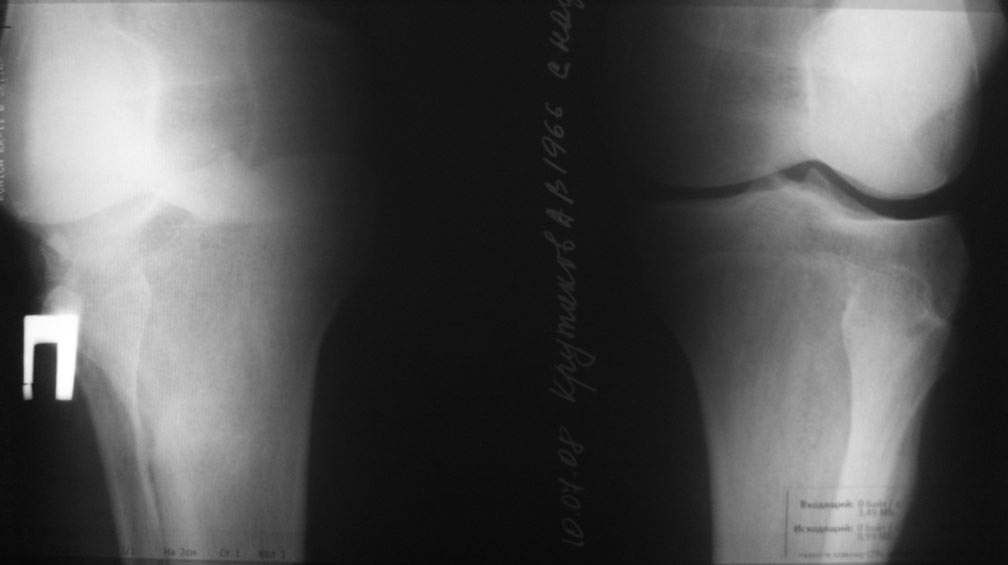

Уважаемый доктор Зайцев! Причина деформации проксимальной тибии у Вашего пациента - преждевременное и несимметричное закрытие зоны роста передней части проксимальной ростковой зоны б/б кости в следствии окультной травмы произошедшей в возрате 10-12 лет. Есть 2 причины рекурвационной деформации в области коленного сустава - мягкотканевая и костная.В данном случае Вы имеете дело не с рукурвацией коленного сустава, а с рекурвационной деформацией проксимальной голени. "Заднего выдвижного положения" на самом деле нет.То, что Вы видите на боковом снимке - это не задний подвывих голени - это снимок, сделанный в сгибании коленного сустава. Дело в том, что костные дефорсации в области коленного хорошо компенсируются за счёт движения в суставе. поэтому то, что вы видите, как задний подвывих на самом деле - сгибательное положение колена.

Это можно проверить очень просто - надо сделать стресс рентгенограмму в положении полного разгибания коленного сустава.Для этого посадите больного на стул, пятку поставьте на другой стул, дайте пациенту кассету 30Х40 держать с наружной стороны колена, и попросить ренгентехника сделать латеральный снимок с втутренней стороны. Сделав снимок здорового колена, Вы сможете расчитать деформацию.

пациент наконец то объявился вновь и мы смогли выполнить новые снимки как лежа так и в нагрузке

если у вас остались силы, давайте обсудим